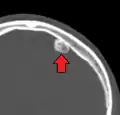

Osteoma of external auditory meatus

An osteoma (plural osteomas or less commonly osteomata) is a new piece of bone usually growing on another piece of bone, typically the skull. It is a benign tumor.